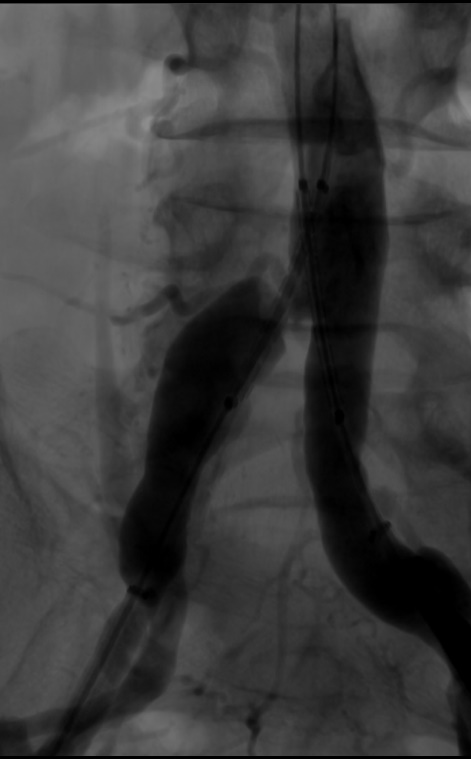

(4)延双侧加硬泥鳅导丝进入LifeStream 10*38mm球扩覆膜支架,再次经双侧长鞘同时造影,明确病变及支架释放位置。

导丝怎么扩【问术ASK】佟铸教授:双侧髂总动脉“对吻”球扩覆膜支架植入术_https://www.jmylbn.com_新闻资讯_第6张